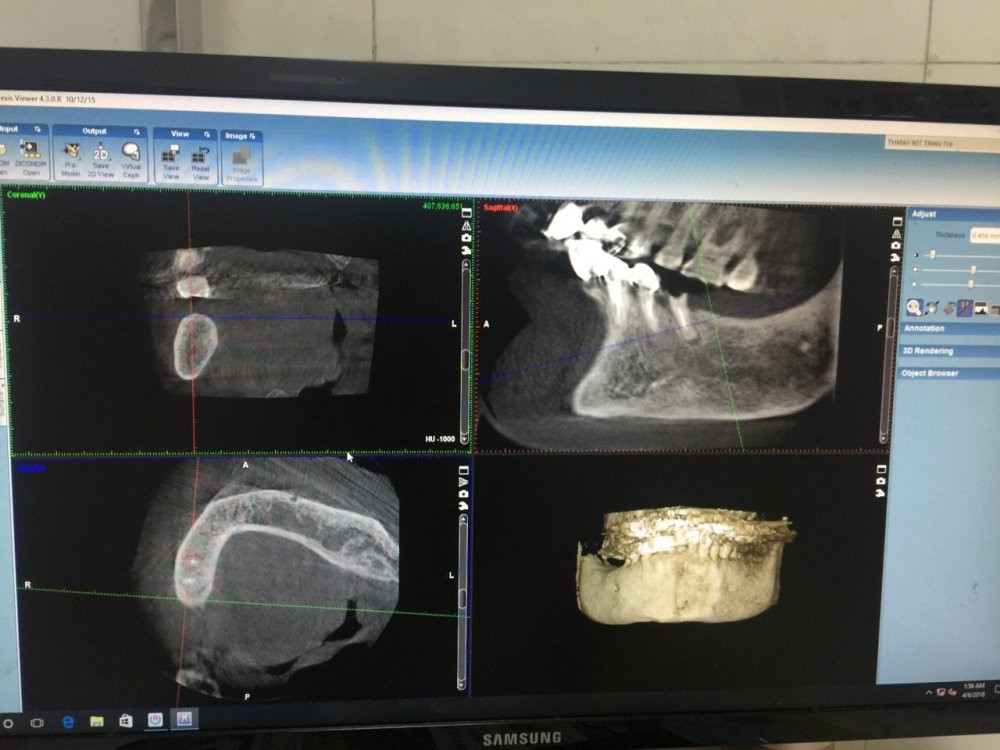

Sau khi thăm khám, các bác sĩ hội chẩn cụ bị gãy chân răng 45 mất răng 46, 47 trên tình trạng toàn thân có cao huyết áp (180/120 mmHg).

Với sự theo dõi chức năng hô hấp, tuần hoàn của bác sỹ gây mê hồi sức, sau 45 phút ê kíp các bác sỹ Khoa Cấy ghép răng implant đã thực hiện phẫu thuật thành công, an toàn 3 implant vào các vị trí răng 45, 46, 47.